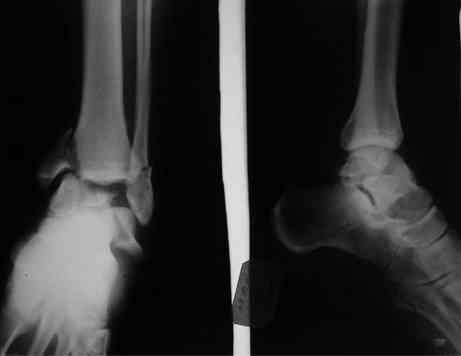

И второй случай из недавней ташкентской практики, (извините за качество ренгенограммы и только в одной проекции) случай падения с высоты (кстати моего друга - известного киноактера) - открытый

смещенный перелом тарана, с переломом переднего края дистального эпиметафиза большеберцовой кости.

При поступлении в приемной сделана первичная обработка с ушиванием открытой латеральной раны и вытяжением за пятку.

Из-за отсутствия времени пришлось оперировать на второе утро, из материала, что имеем на месте, фиксирован двумя шурупами, а третий-это контур сломанного жойстика в 4 мм. На дистальный медиальный конец тибиа antiglide 3.5 мм пластина. Через пару дней выписан и несмотря на предупреждение, самостоятельно начал нагрузку в 4 недели, время не ждет, снимается в боевике в Росийской Федерации.

Для оценки состояния нужны дополнительные исследования, например

> Canale или Broden ренгенограммы

повторили рентгенограммы и доделали проекции, к единому мнению все еще не пришли